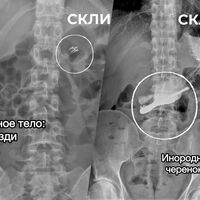

НИИ скорой помощи имени Н.В. Склифосовского опубликовал подборку самых необычных предметов, которые врачи извлекли из пациентов в 2025 году. Список появился в Telegram-канале медицинского учреждения.

По данным клиники, за год медикам приходилось удалять беспроводные наушники, зубные коронки, абрикосовую косточку, черенок ложки, украшения и даже гвозди, которые пациенты случайно проглатывали, в том числе во время ремонтных работ.

В институте отметили, что подобные случаи выглядят курьезно, однако проблема остается серьезной. Ежегодно в Склиф поступают десятки пациентов с инородными телами в организме. Таким людям требуется экстренная медицинская помощь, а в ряде случаев — длительное восстановление после вмешательства.